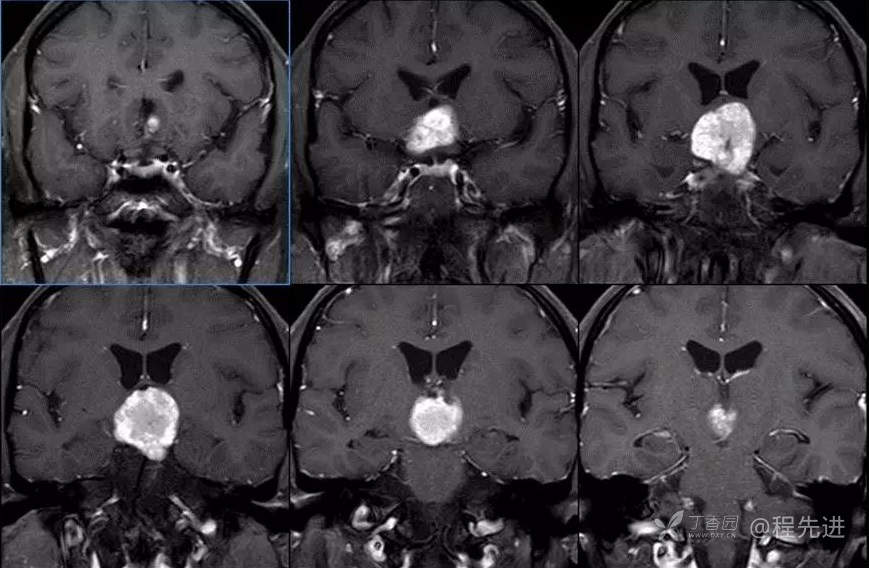

图像依次为T1横断位、T2横断位、T2FLAIR横断位、T2冠状、T1矢状、T1增强横断、矢状、冠状位